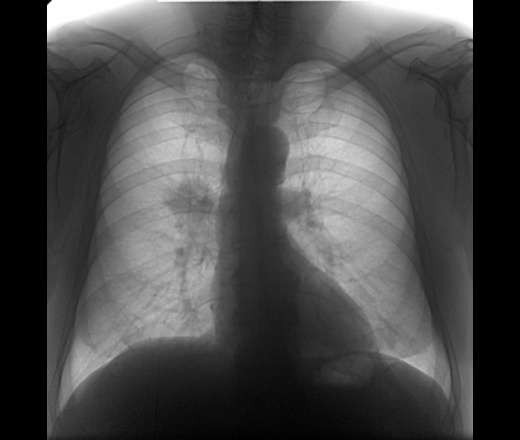

Пол пациента: Мужской пол Тип патологии: Злокачественное новообразованиеДругое Область исследования: Грудная клетка и верхние дыхательные пути Методы исследования: Rg Мужчина 70 лет. Проф. Флг. Центральный C-R ? На боковом снимке в каком сегменте это образование? Ваше мнение коллеги? ID:80919 Цель публикации: Консультация Втр, 19/03/2019 - 22:01 #1 NIL Не на сайте Был на сайте: 1 день 8 часов назад Зарегистрирован: 25.11.2013 - 20:50 Публикации: 18206 За центральный C-r. Болше в S3 "Слушай всех, прислушивайся к немногим, решай сам".© Втр, 19/03/2019 - 22:50 #2 Сергей Кузьминов Не на сайте Был на сайте: 1 год 2 недели назад Зарегистрирован: 06.10.2012 - 15:51 Публикации: 11813 NIL wrote: За центральный C-r. Болше в S3 И КТ надобна. Втр, 19/03/2019 - 22:54 #3 И.Бондаренко Не на сайте Был на сайте: 10 часов 20 минут назад Зарегистрирован: 13.09.2011 - 22:55 Публикации: 9206 NIL wrote: За центральный C-r. +1 Втр, 19/03/2019 - 23:06 #4 Игорь Ким Не на сайте Был на сайте: 1 год 3 месяцев назад Зарегистрирован: 17.10.2014 - 17:30 Публикации: 4672 NIL wrote: За центральный C-r. +1. Не могу исключить S6. Ср, 20/03/2019 - 03:09 #5 Lory Не на сайте Был на сайте: 4 месяцев 4 недели назад Зарегистрирован: 02.03.2016 - 18:28 Публикации: 766 Игорь Ким wrote: NIL wrote: За центральный C-r. +1. Не могу исключить S6. +1, Тоже вижу в S6 Ср, 20/03/2019 - 12:11 #6 В.И. Не на сайте Был на сайте: 1 месяц 4 недели назад Зарегистрирован: 22.09.2015 - 17:55 Публикации: 2321 Всем спасибо.

За центральный C-r. Болше в S3

+1. Не могу исключить S6.

+1, Тоже вижу в S6